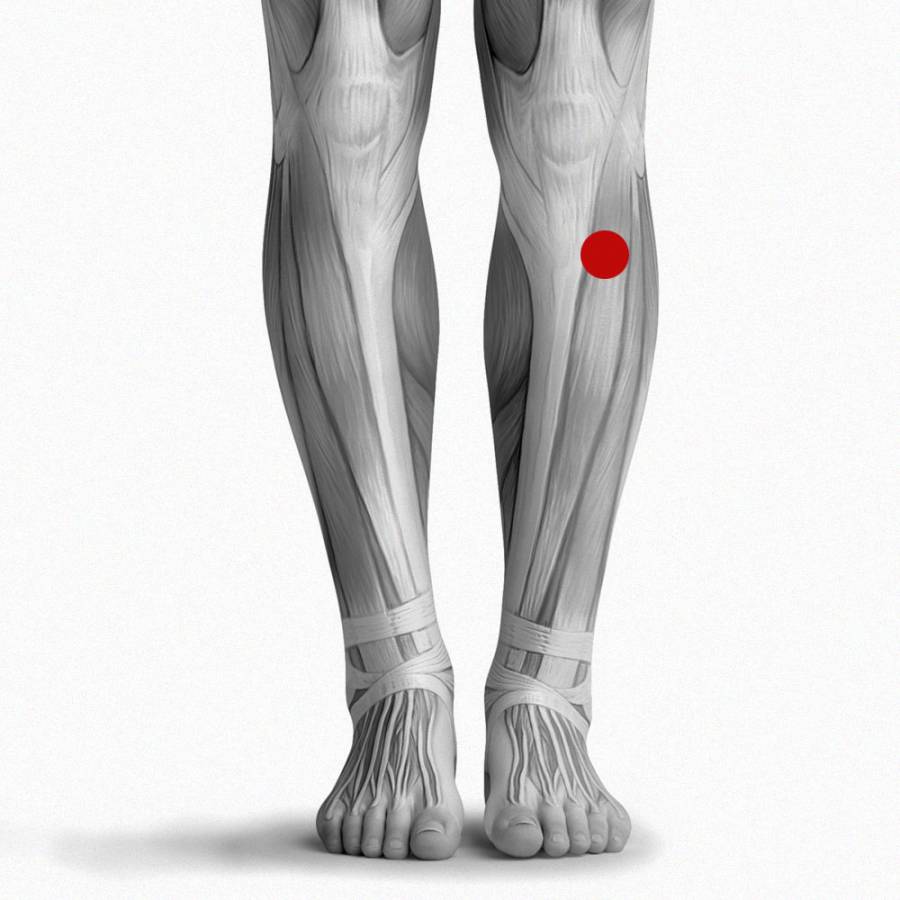

Возможные причины болей в ноге ниже колена и рекомендации